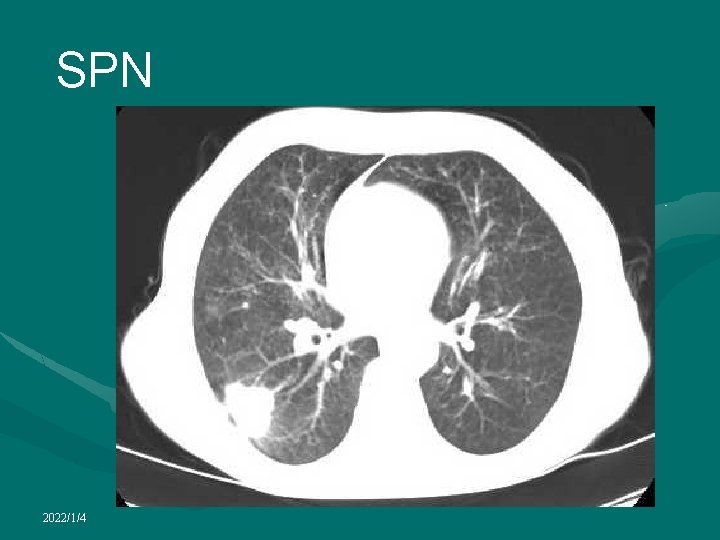

Solitary pulmonary nodule • A well-circumscribed round or oval-shaped lesion measuring less than 3 cm in diameter • Common finding on routine screening chest radiograph in adults • vast majority of such incidentally detected lesions are benign • Most common radiological manifestation in patients with asymptomatic lung cancer • Almost always benign in patients under 30. • but should be followed for at least 2 years. • At the age of 40 and beyond, the likelihood of malignancy is increased • Most prove resectable, early diagnosis remains essential 2022/1/4

Solitary pulmonary nodule • CT is almost always obtained in the diagnostic work-up of SPN • Radiological factors most often considered useful in determining nature of a SPN: • lesion size • Nodule margins and contours can be classified as smooth, lobulated, irregular, or spiculated • growth rate • presence of calcification 2022/1/4

Solitary pulmonary nodule • Likelihood of malignancy in an indeterminate SPN detected by chest radiography is a direct function of the size of the lesion • Large majority of nodules > 2 cm are malignant while only about 50% of nodules < 2 cm are malignant • Pulmonary malignant nodules often appear ill-defined and/or irregular in shape • A spiculated appearance on HRCT strongly suggests malignancy • Benign nodules are often well-defined, round and smooth in contour • However, solitary pulmonary metastases may have the same appearance 2022/1/4

Solitary pulmonary nodule • Air bronchograms within a nodule are more common in malignancies than in benign nodules and more suggestive of adenocarcinomas or bronchioalveolar cell carcinomatosis • Cavitation is also more common in malignant nodules than benign nodules • But focal benign pulmonary lesions such lung abscess can also cavitate • Satellite nodules in association with an SPN suggest granulomatous disease • Skip metastases around a bronchogenic carcinoma cannot be ruled out 2022/1/4

SPN 2022/1/4